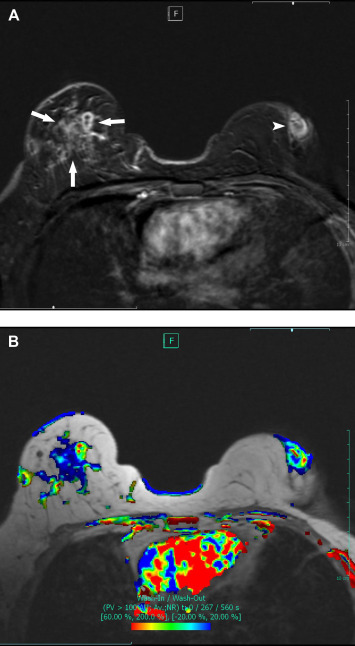

The most useful method for evaluating the radiologic appearance of IGM is sonography. The technique defines valuable data for infectious conditions such as effusions, inflammation of parenchyma and fatty tissues, abscess formations, fistula tracts. These are the key findings for discriminating the suspected lesions from malignancy. Information of the patients' history is essential to assess before evaluation. Sonography examination showed a hypoechoic collection in nine patients (90%), solid lesion in one patient (10%), thickening of the breast skin in eight patients (80%), fistula tracts in four patients (40%), and ductal fillings and postobstructive dilatation in three patients (30%). Mammographic findings were nonspecific in the three patients who underwent mammograms. Magnetic resonance imaging (MRI) evaluation may demonstrate the extension of the disease and may be used to clarify the suspected diagnosis. MRI was performed for three cases; asymmetrical enhancement with nonspecific contrast enhancement kinetics and fluid collections were common.

(A,B) MRI images of bilateral IGM. (A) Contrast enhanced T1 weighted reformat ...

Figure 3.

(A,B) MRI images of bilateral IGM. (A) Contrast enhanced T1 weighted reformat substraction (2nd minute) image shows wide asymmetrical nonmass enhancement in right breast and retroareolar disease in left. (B) Corresponding color overlay T1 weighted axial scan provided by the computer-aided diagnosis (CAD) system represents nonspecific contrast enhancement kinetics in both breasts. IGM = idiopathic granulomatous mastitis; MRI = magnetic resonance imaging.